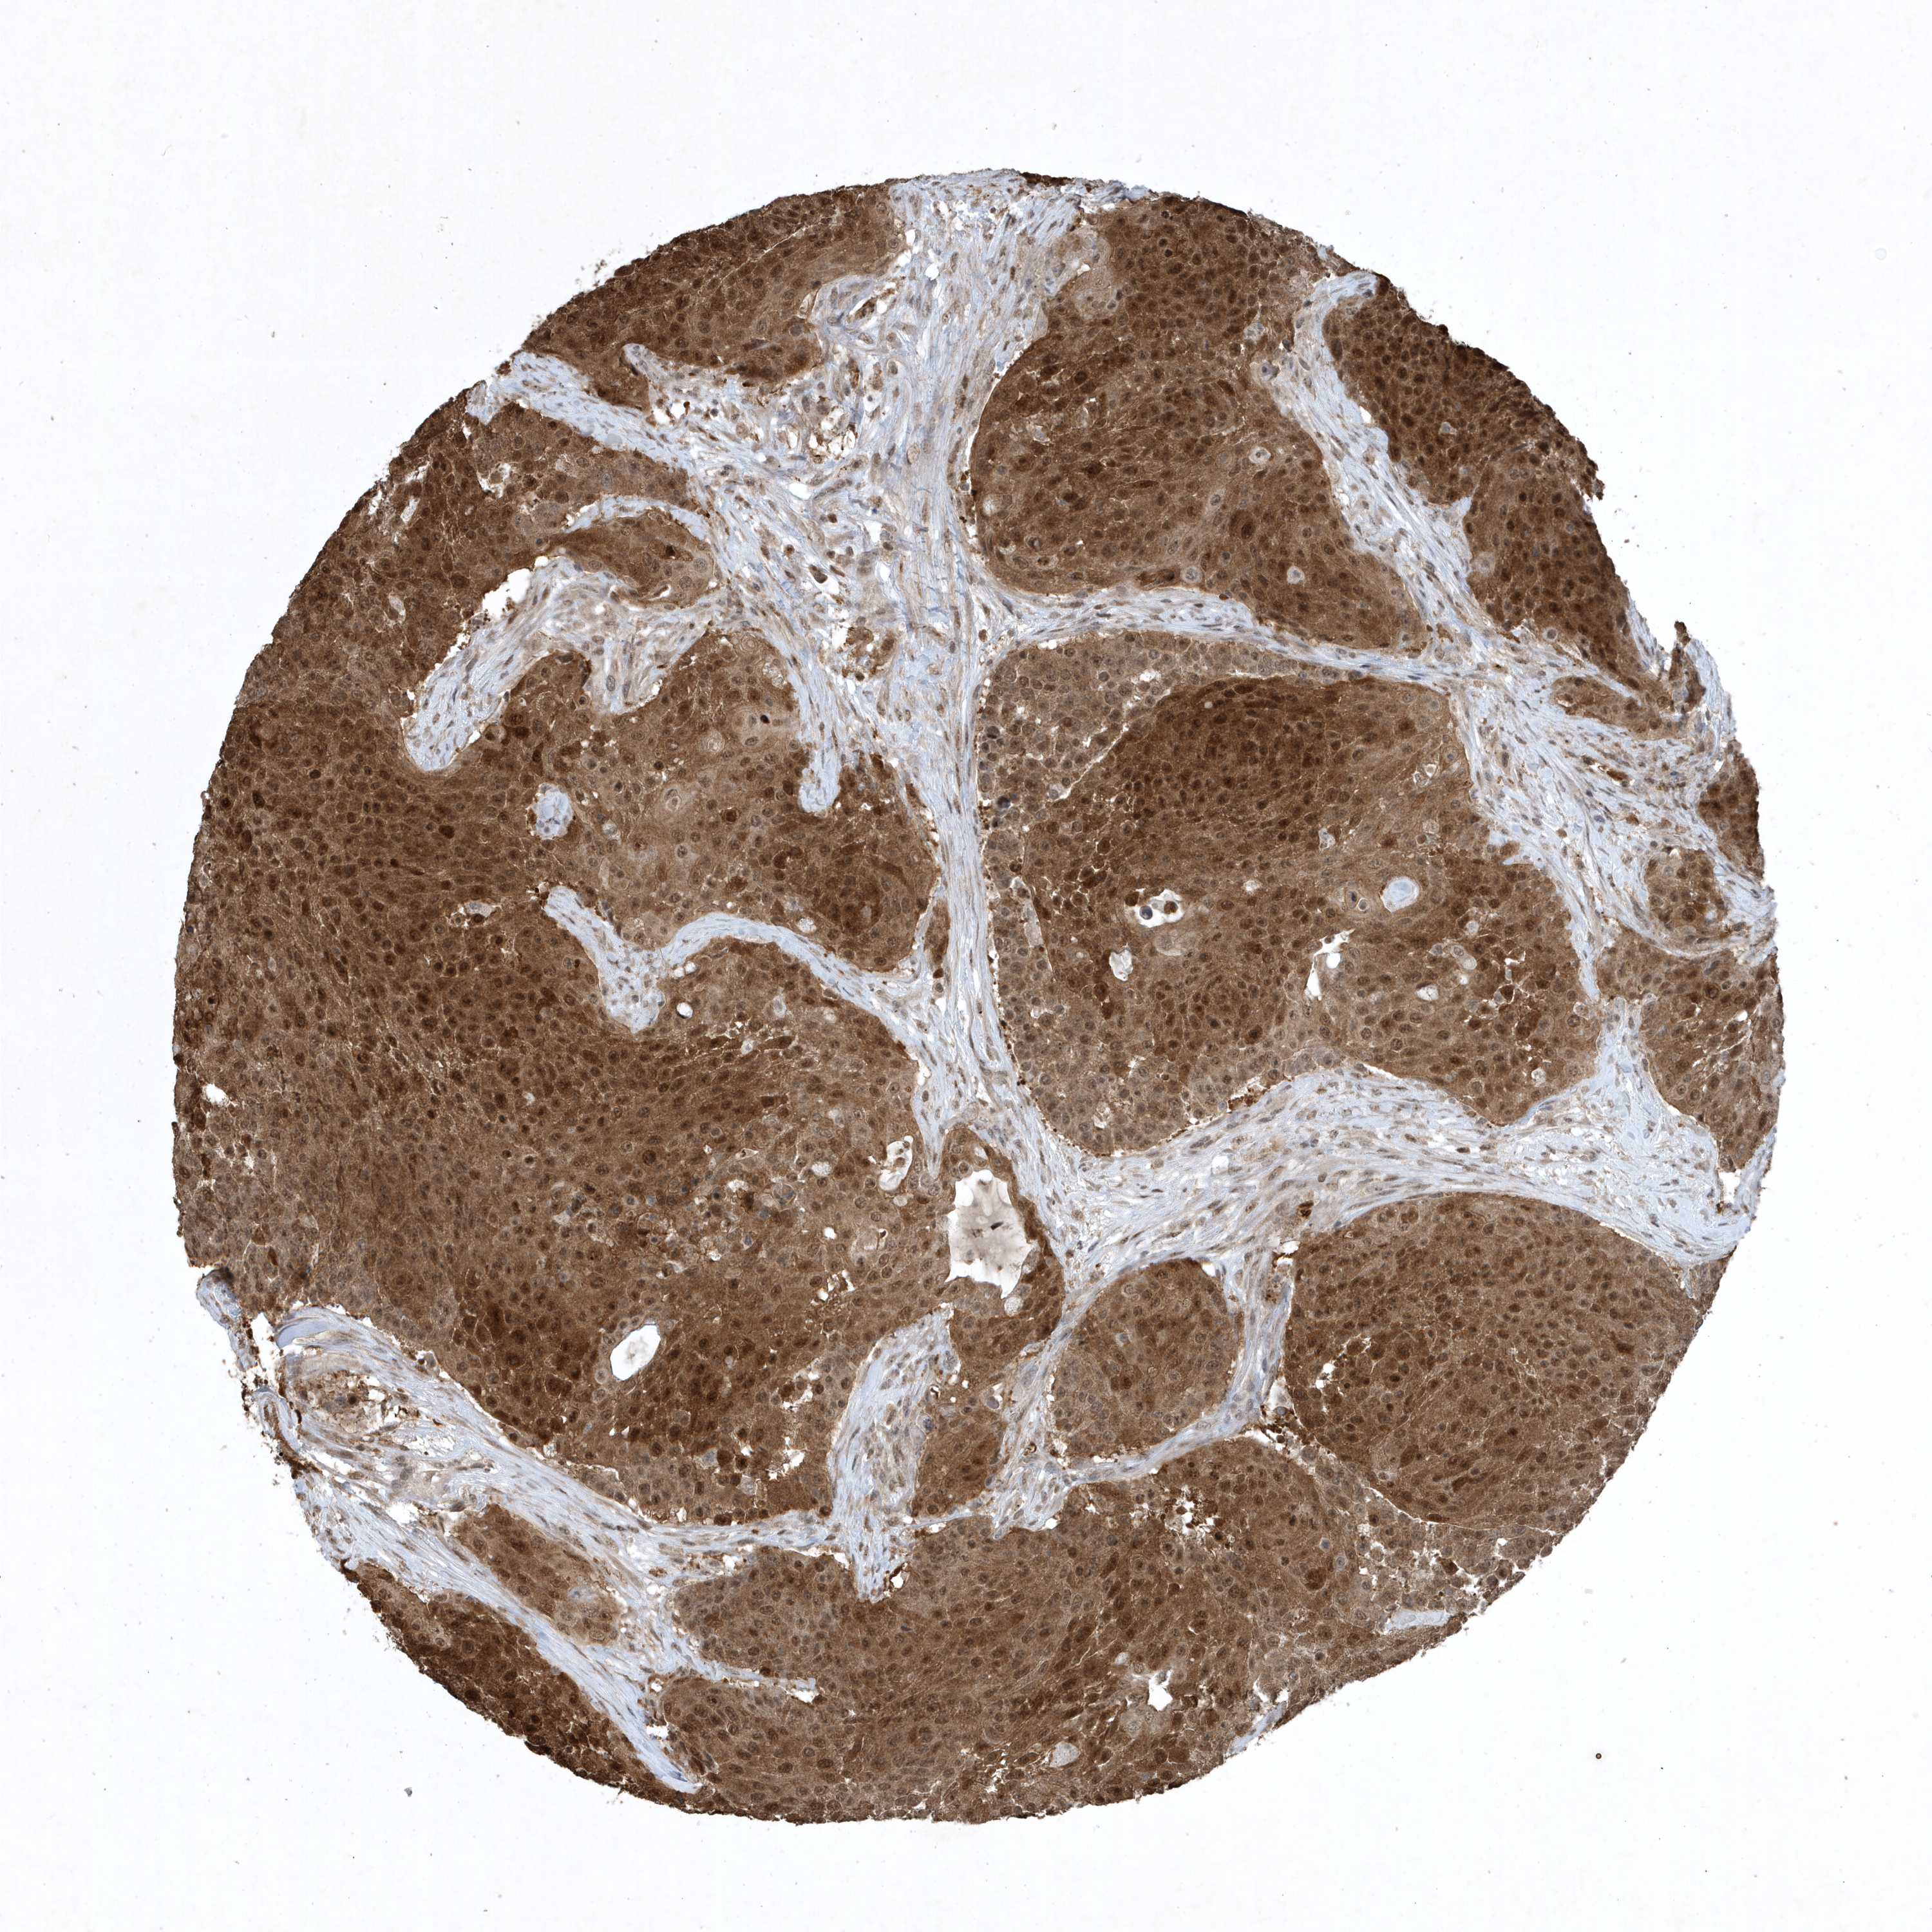

UROTHELIAL CANCER - Protein expressioni

A mouse-over function shows sample information and annotation data. Click on an image to view it in a full screen mode. Samples can be filtered based on level of antibody staining by selecting one or several of the following categories: high, medium, low and not detected. The assay and annotation is described here.

Note that samples used for immunohistochemistry by the Human Protein Atlas do not correspond to samples in the TCGA dataset.

Antibody stainingi

Antibody staining in the annotated cell types in the current human tissue is reported as not detected, low, medium, or high, based on conventional immunohistochemistry profiling in selected tissues. This score is based on the combination of the staining intensity and fraction of stained cells.

Each image is clickable and will lead to virtual microscopy that enables deeper exploration of all samples and also displays staining intensity scores, fraction scores and subcellular localization as well as patient and tissue information for each sample.

Antibody HPA052504

Antibody CAB017451

Antibody CAB032815

Staining

High

Medium

Low

Not detected

Intensity

Strong

Moderate

Weak

Negative

Quantity

>75%

75%-25%

<25%

None

Location

Nuclear

Cytoplasmic/membranous

Cytoplasmic/membranous,nuclear

Urothelial carcinoma, High grade

Urothelial carcinoma, NOS

Urothelial carcinoma, Low grade